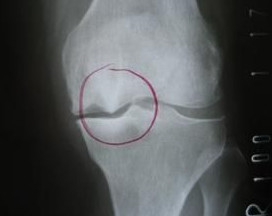

人体的骨、关节、肌腱、肌、韧带、筋膜、滑囊及其相关的血管、神经等,对长期、反复、持续的姿势或职业动作在局部形成慢性损伤,这些损伤会引发局部的炎症,这样的炎症状态就会表现为受损的部位发红、肿胀、发热并且产生疼痛。这种疼痛多为无菌性炎症(非细菌、病毒等微生物引发的感染性炎症)所致,严重时会影响我们的工作和生活。这种慢性炎症会引发受损组织自我修复,而炎症部位修复的“矫枉过正”就是“增生”,骨组织炎症后修复所导致的增生被称之为“骨质增生”,而骨刺,就是骨质增生的俗称,是常见的骨科疾病。引起骨质增生病因有很多,并非只有老年人才会罹患,年轻人也会有,比如青年运动员长期运动劳损引发的骨质增生。

骨刺本身不会消除(手术清除除外),但是骨刺也并非是组织正常状态,所以当骨刺引发慢性炎症急性加重,伴随着难以忍受的疼痛时,医师可能就要考虑使用以改善炎症控制疼痛为目的“封闭治疗”了。

封闭针在骨科应用非常广泛。如网球肘、足跟痛、桡骨茎突炎、膝关节滑膜炎等。